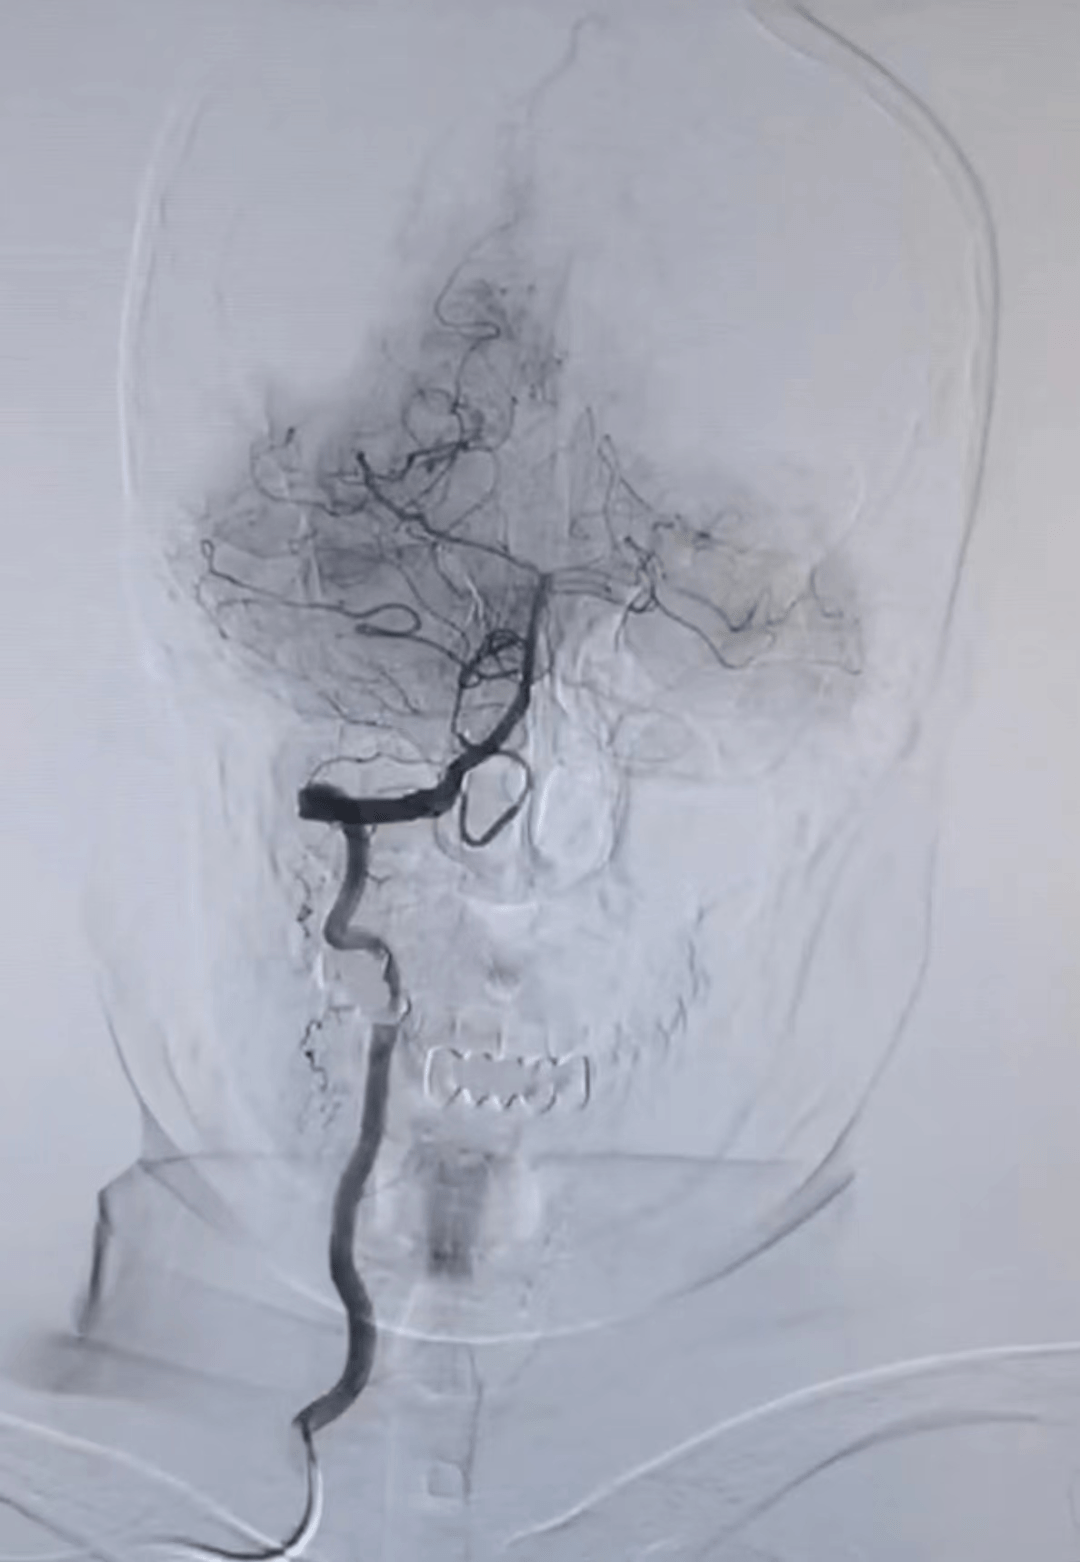

术前脑血管造影

图片尺寸3025x4032